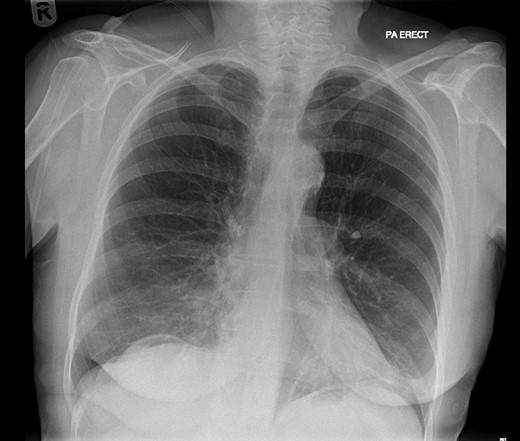

On examination, she was febrile. Her abdomen was generally tender. Bowel sounds were present and up to that time her stoma was working. Her perineal hernia was red and tender. Her initial CXR (Fig. 1) did reveal a sliver of gas underneath her right hemidiaphragm and in keeping with her abdominal findings she progressed to further imaging. CT abdomen pelvis with contrast showed pneumoperitoneum (Fig. 2) with ‘a tiny pocket of air is also seen adjacent to a loop of bowel in the pelvis posterior to the bladder’. ‘Exact site of perforation has not been demonstrated but could possibly be in the bowel loops in the perineum’ (Figs 3 and 4).

CT showing small bowel loops in pelvis with perineal hernia and free fluid.